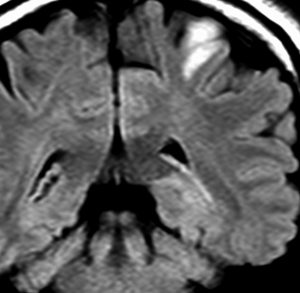

グリオマトーシス gliomatosisのような例

病理組織診断で退形成性星細胞腫 WHO grade IIIとされるものに,全く違った性質を示すグリオーマがあります。

ゆっくり進行する軽い右麻痺で発症した50歳くらいの患者さんです。脳梗塞や脱髄疾患を疑われていました。左頭頂部皮質下から脳梁,内包,中脳大脳脚まで非常に広範囲に浸潤しています。single cell infiltrationという浸潤形態を想像させます。右下はT!ガドリニウム造影で,この部分だけが増強所見があります。

おそらく今後は,diffuse hemispheric glioma WHO grade 4と診断されます。

軽度の異型性を認め,細胞密度が高く核分裂が目立ち,Ki-67 (MIB)染色率は20%に達しました。1p/19q欠失はなくMGMTメチレーションもありませんでした。IDH変異は調べていない年代の例で不明です。病理組織診断でanaplastic astrocytomaとされました。治療は,全脳に近い照射野となるので50Gy/25分割が限界でした。TMZを併用しています。

照射後も症状は一度も改善することなく悪化して,数ヶ月後にはもともと腫瘍が見えなかった内側側頭葉に大きな腫瘍塊が発生増大しました。この例は退形成性星細胞腫と診断するしかなかったものですが,2020年時点でははっきり分類できない星細胞系腫瘍です。